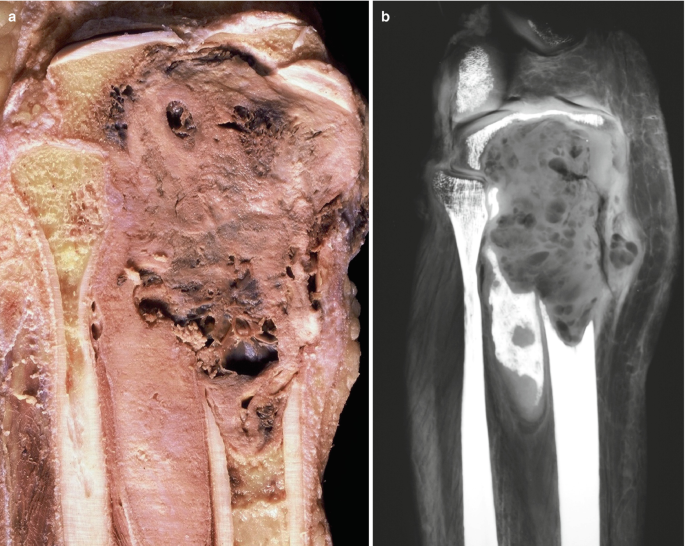

Fibrosarcoma is a rare malignant tumor that arises from fibroblasts, the cells that produce connective tissue. It can occur in soft tissues or bones, affecting both children (infantile/congenital type) and adults (typically in deep soft tissues of limbs or trunk).

• Physical exam and imaging (MRI, CT scan)

• Histopathology to distinguish from other soft tissue sarcomas